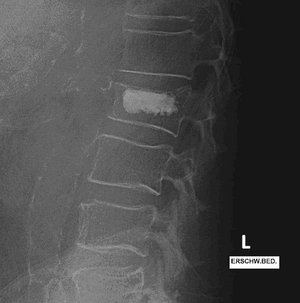

Röntgenbild der Lendenwirbelsäule zeigt Wirbelkörper und Bandscheiben deutlich.

Osteoporotisch bedingte LWK 2-Fraktur

Röntgenbild der Lendenwirbelsäule mit Wirbelkörperfraktur und Kyphoplastie.

Stabilisierung des Wirbelkörpers mittels Kyphoplastie LWK 2